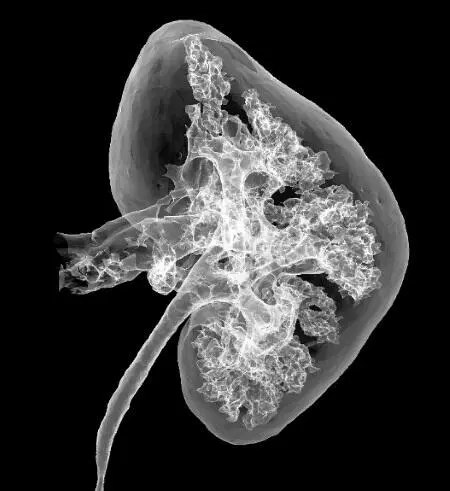

На этой компьютерной томограмме видны корковый и мозговой слои, почечные чашки, ворота почки, центральная часть почки с впадающими/выходящими кровеносными сосудами, нервами и мочеточник.

Нефрон является основной структурно-функциональной единицей почки и образует ее тканевый каркас.